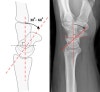

* Scapholunate angle

Normal : 30 - 60°

Questionably abnormal : 60 - 80°

Abnormal : > 80° indicates instability of the wrist.

* Scaphoid axis

The line through the midpoints of its proximal and distal poles.

Since the midpoint of the proximal pole is often difficult to appreciate, an almost parallel line can be used that is traced along the most ventral points of the proximal and distal poles of the bone.

* Lunate axis

The axis of the lunate runs through the midpoints of the convex proximal and concave distal joint surfaces and can best be drawn by finding the perpendicular to a line joining the distal palmar and dorsal borders of the bone as demonstrated on the left.